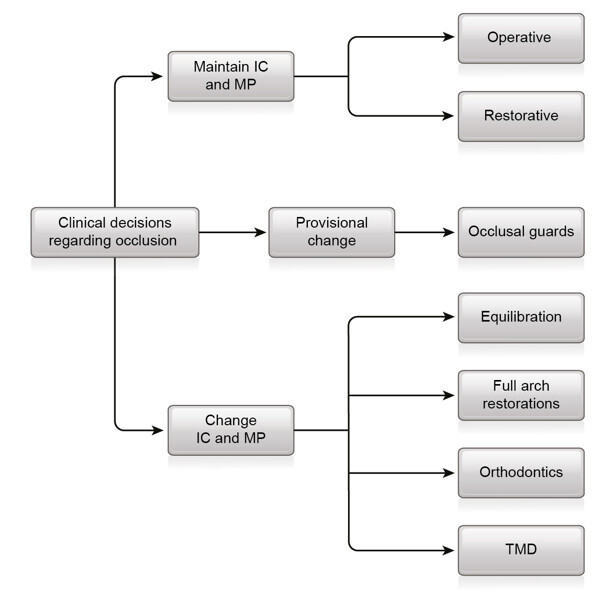

Fig. 12: Clinical decisions regarding occlusion. IC = intercuspation; MP = mandibular position; TMD = temporomandibular joint dysfunction syndrome.